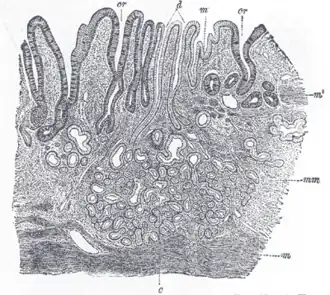

Het maagslijmvlies, ook wel mucosa genoemd, is een laag goed doorbloed weefsel in de maag. Dit slijm dient ter bescherming van de maagwand, met name tegen de bijtende werking van maagzuur en met ingenomen voedsel meegekomen bacteriën. Medicijngebruik van bijvoorbeeld pijnstillers of bijnierschorshormonen kan deze slijmproductie nadelig beïnvloeden, en daarmee de kans op een maagzweer of maagbloeding vergroten.